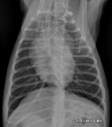

Quel est votre diagnostic ?

RadioQuiz 30 – C’est parce qu’il fait frette que mon pitou tousse docteur ?

RadioQuiz 28 – Un coeur sous la masse

RadioQuiz 26 – Une balade qui fait grogner